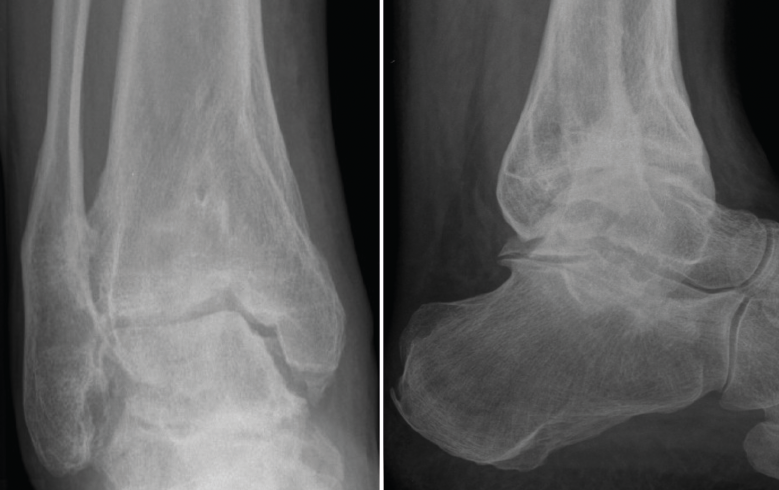

Figura 1. Artrosis de tobillo en varo grado 3A de Tanaka.

La meta de la SMOT es la reconstitución o modificación del eje del tobillo para modificar la carga articular y, de esta manera, disminuir o retrasar la progresión de la lesión al cartílago articular(15,16,17,18). Dependiendo de los grados necesarios para la corrección, la osteotomía puede ser conformada por una cuña de apertura medial (Figuras 1 y 2) o, si se requieren > 10° de corrección o una sindesmosis fusionada, una cuña de cierre lateral para evitar una discrepancia de longitud importante(19). Cualquiera que sea la técnica, suele incluirse osteotomía del peroné en ambos casos. Si el peroné tiene claramente una longitud mayor a la fisiológica, restaurar la posición neutra del astrágalo resulta imposible. Knupp et al.(20) realizaron una modificación a la clasificación de la artrosis en varo de tobillo mediante la adición de un algoritmo de tratamiento para los procedimientos extraarticulares. Esta nueva clasificación permite categorizar los distintos tipos de artrosis de tobillo en varo y facilita la decisión terapéutica, especialmente cuando una SMOT aislada resulta insuficiente. Por otra parte, se puede añadir a este procedimiento una osteotomía intraarticular (plastia de pilón tibial o plafonplastia) si se observa persistencia de la inclinación astragalina por artrosis unicompartimental (Figura 3).